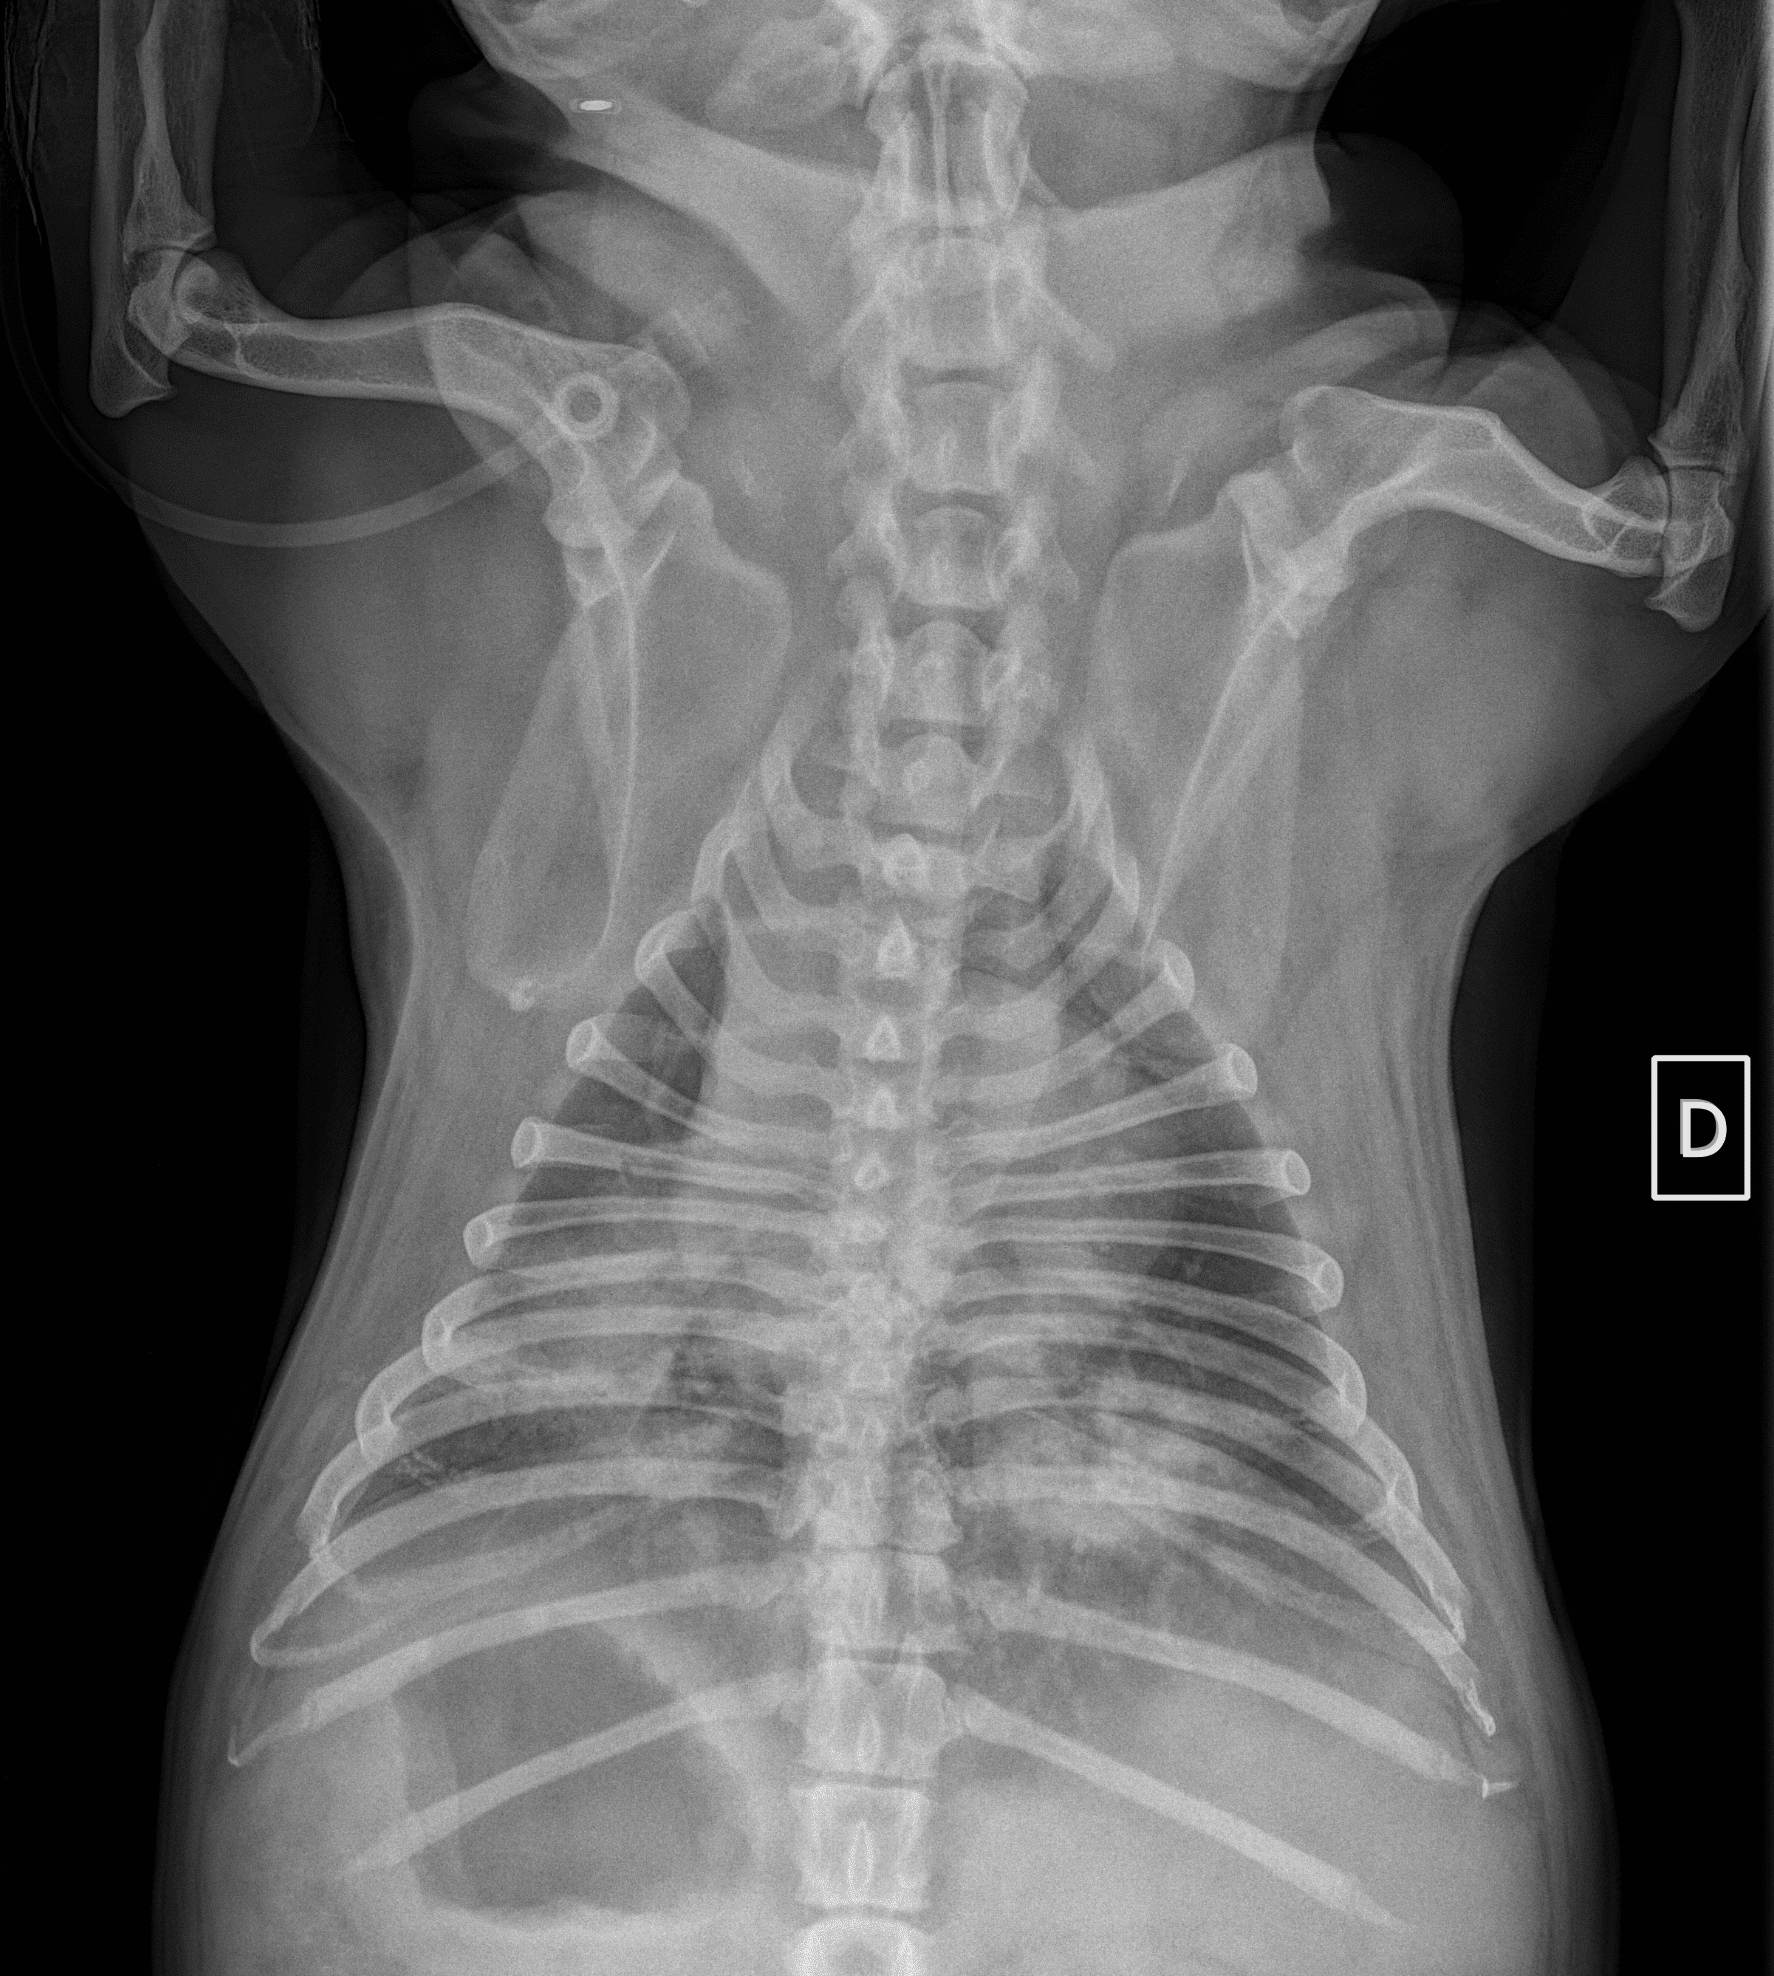

Leptospirose chez le chien